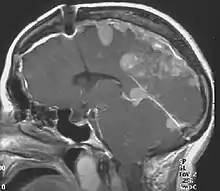

![]() | |

| Figure of various morbidities associated with neurofibromatosis type II.[1] | |